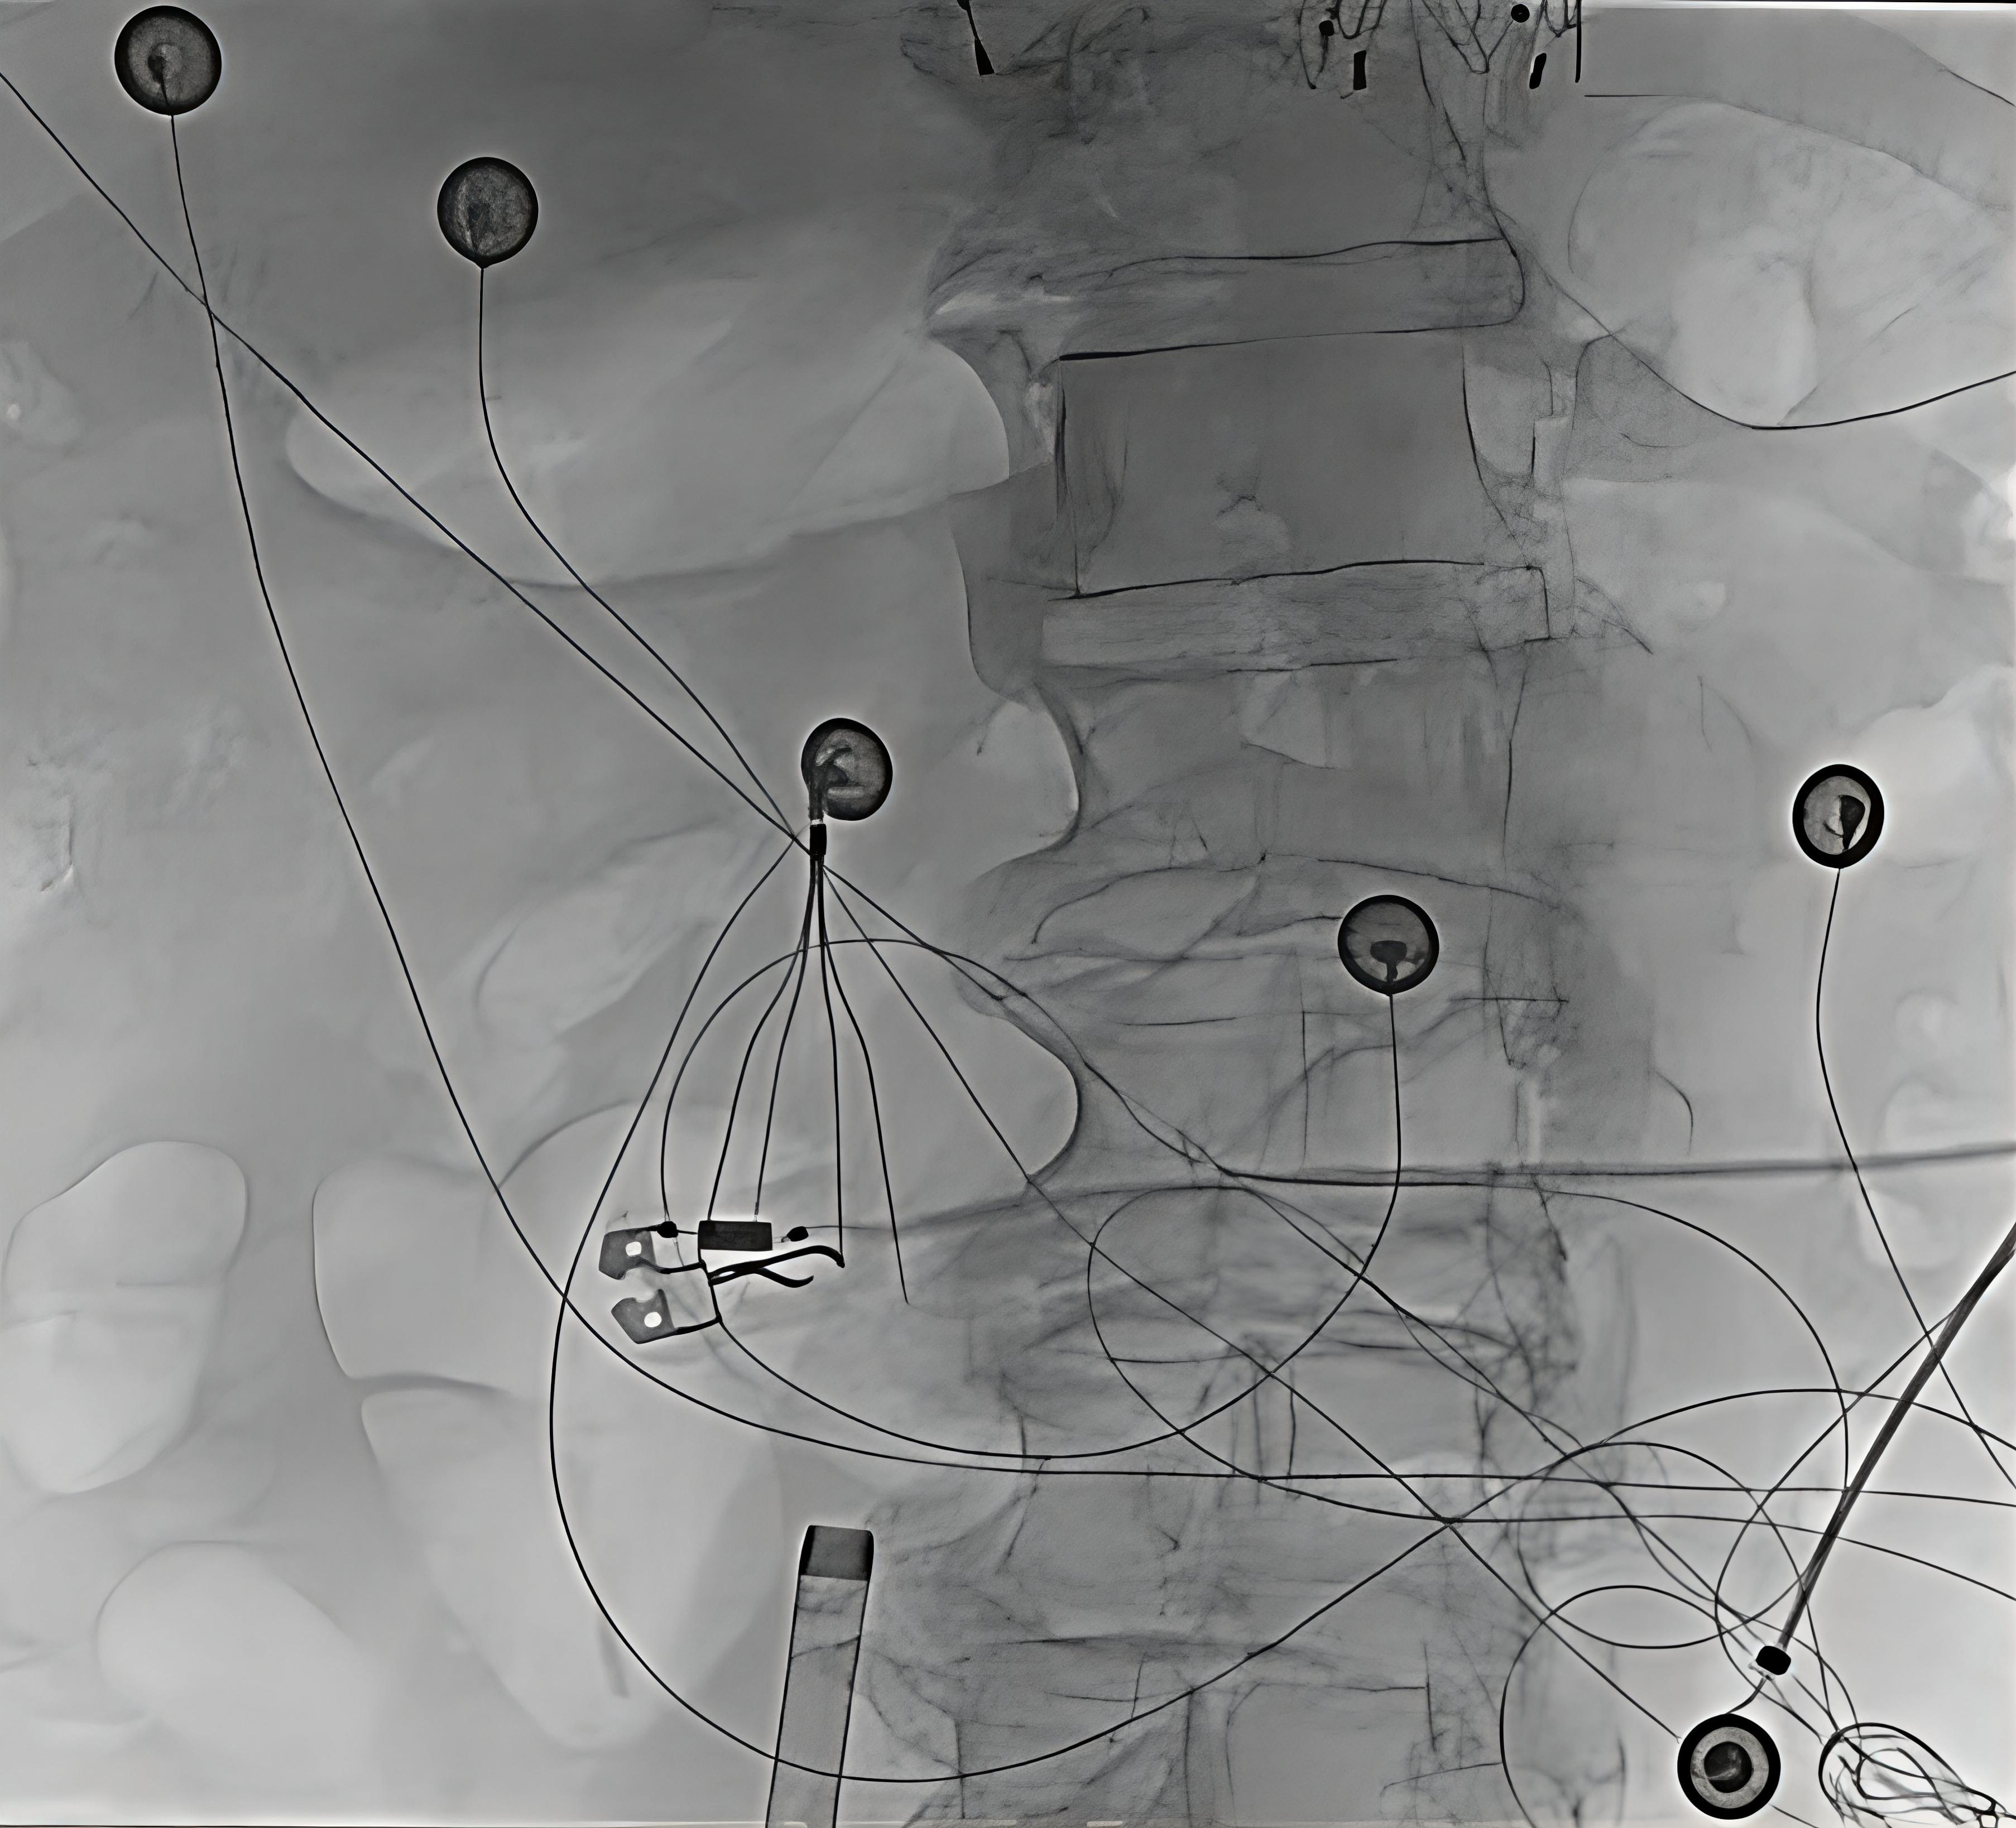

Pulmonary vein isolation was subsequently performed using pulsed field ablation (PFA) via the right internal jugular (RIJ) vein. RIJ access was obtained under ultrasound guidance. Transesophageal echocardiography excluded intracardiac thrombus and guided transseptal puncture using an Agilis steerable sheath (Abbott), ProTrack pigtail wire (Baylis), and a Bovie device (Medtronic Covidien). Because the superior route requires approaching the fossa ovalis from above, operators must work through a steeper and less favorable transseptal angle, and catheter manipulation can be more challenging. Awareness of reduced catheter stability, as well as the altered torque response and fluoroscopic orientation inherent to a superior-only approach, was important for navigation of the left atrium. Heparin was administered to maintain an activated clotting time of 300 to 350 seconds. The sheath was then exchanged for the FARAPULSE system (Boston Scientific), and all 4 pulmonary veins were successfully isolated with demonstration of exit block (Figure 2). PFA was selected for its tissue-selective, non-thermal mechanism that reduces collateral injury risk. Post-procedure electrocardiography showed atrial pacing with left axis deviation and left bundle branch block.

As electrophysiology procedures expand, more patients present without safe femoral access. In carefully selected cases, superior venous access can be a viable alternative when femoral access is limited by IVC filters, venous thrombosis, chronic occlusion, prior vascular surgery, or congenital IVC interruption. This report illustrates a novel alternative access strategy for FARAPULSE pulmonary vein isolation that was performed safely and effectively via the right internal jugular vein.